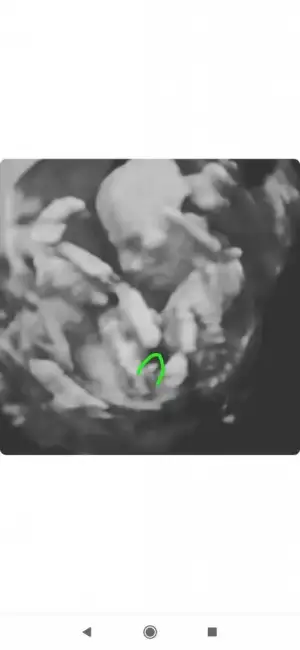

Ben cizmedim isegramdan bu sayfa çizdi cinsiyetini öğren diye bi sayfaSen ustunu cizmissin bilemedim simdi.baska bir dr a da gitsen imkanın vaktin varsa için rahat olur .

Evet o sayfa bana erkek dedi bugün öğrenmeye gideceğim bende hayırlısı olsunBen cizmedim isegramdan bu sayfa çizdi cinsiyetini öğren diye bi sayfa